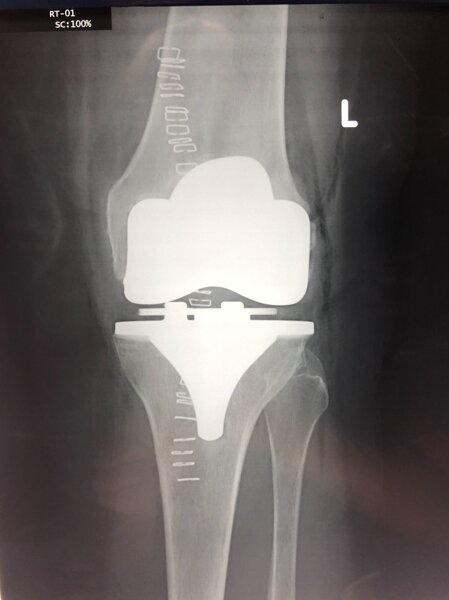

La protesi di ginocchio consiste in un rivestimento completo o parziale dell'articolazione, quindi ricoprendo sia la superficie articolare della tibia che quella del femore. A discrezione del chirurgo ed in base al caso specifico si può rivestire anche la rotula. Volendo semplificare la procedura di impianto di una protesi di ginocchio si possono individuare alcuni passaggi dell'intervento:- preparazione delle superfici ( si asportano i residui di cartilagine, esponendo l'osso sub-condrale in modo da avere una base di appoggio uniforme per la protesi )

-impianto delle componenti metalliche ( si impiantano due componenti metalliche articolari una per il femore e l'altra per la tibia, che costituiranno la nuova articolazione )

-posizionamento dell'inserto ( tra le due componenti metalliche del femore e della tibia viene posizionato un inserto in polietilene cioè una plastica ad alto peso molecolare, per curare la superficie di scorrimento ed ammortizzare i carichi, per sostituire la funzione dei menischi, l'inserto può essere fisso oppure mobile attorno ad un perno centrale )

-impianto della rotula ( si può decidere o meno in base al caso specifico se impiantare la protesi della rotula a seconda delle condizioni della cartilagine e della sintomatologia del paziente )

Intervento sicuro, elimina il dolore e corregge eventuali deformità della gamba. Dopo questo intervento potrai riprendere la tua vita di sempre e le normali attività senza dolore.